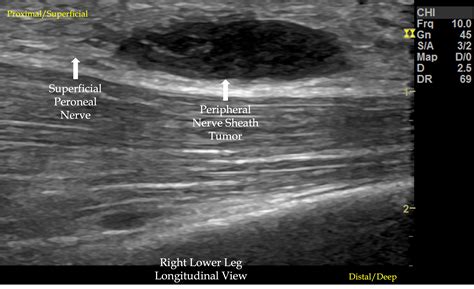

Nerve Pain In Foot